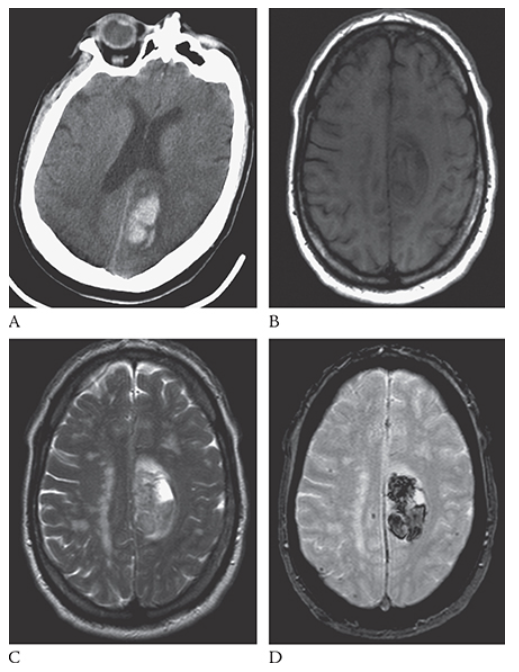

Intracerebral Hemorrhage. Axial NECT shows a large hyperdense region in the right parietal lobe consistent with acute hemorrhage. This is surrounded by low-attenuation cerebral edema. Note the mass effect and midline shift.